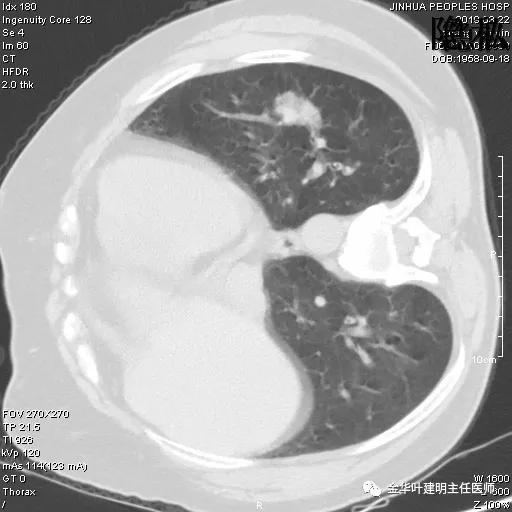

可见左肺下叶比较靠中央的部位也有一病灶,是混合磨玻璃影,偏实性,瘤肺边界清楚,是较为典型的肺癌表现。进一步的靶扫描图像如下:

靶扫描更清晰的显示细节,从影像上看,基本可以断定左下肺的是恶性肿瘤了,而且已经密度较高,长径也在3厘米以上,不能继续观察等待了!